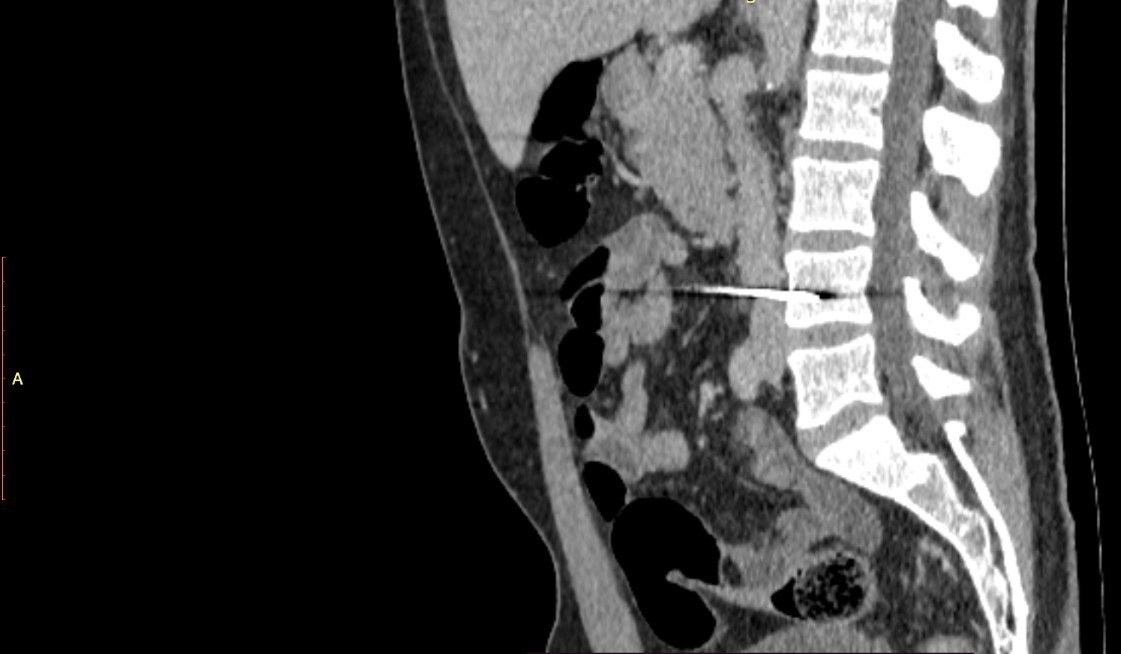

Врачи выяснили, что стрела прошла через нижнюю полую вену и застряла в теле поясничного позвонка. Спинной мозг пациента не был поврежден. Хирурги Елизаветинской больницы провели операцию через срединную лапаротомию. Они сделали разрез живота в направлении от грудной клетки к пупку.

Вдоль раневого канала был осуществлен доступ к нижней полой вене, которая в дальнейшем была полностью выделена от окружающей ткани. Снаряд удалили и отверстие в вене аккуратно ушили. Следующим важным этапом была ревизия кишечника: тонкой и толстой кишки и всех органов брюшной полости. Были выявлены три отверстия в брюшине, которые также аккуратно были ушиты. Леонид Макар, сердечно-сосудистый хирург кардиохирургического отделения №1